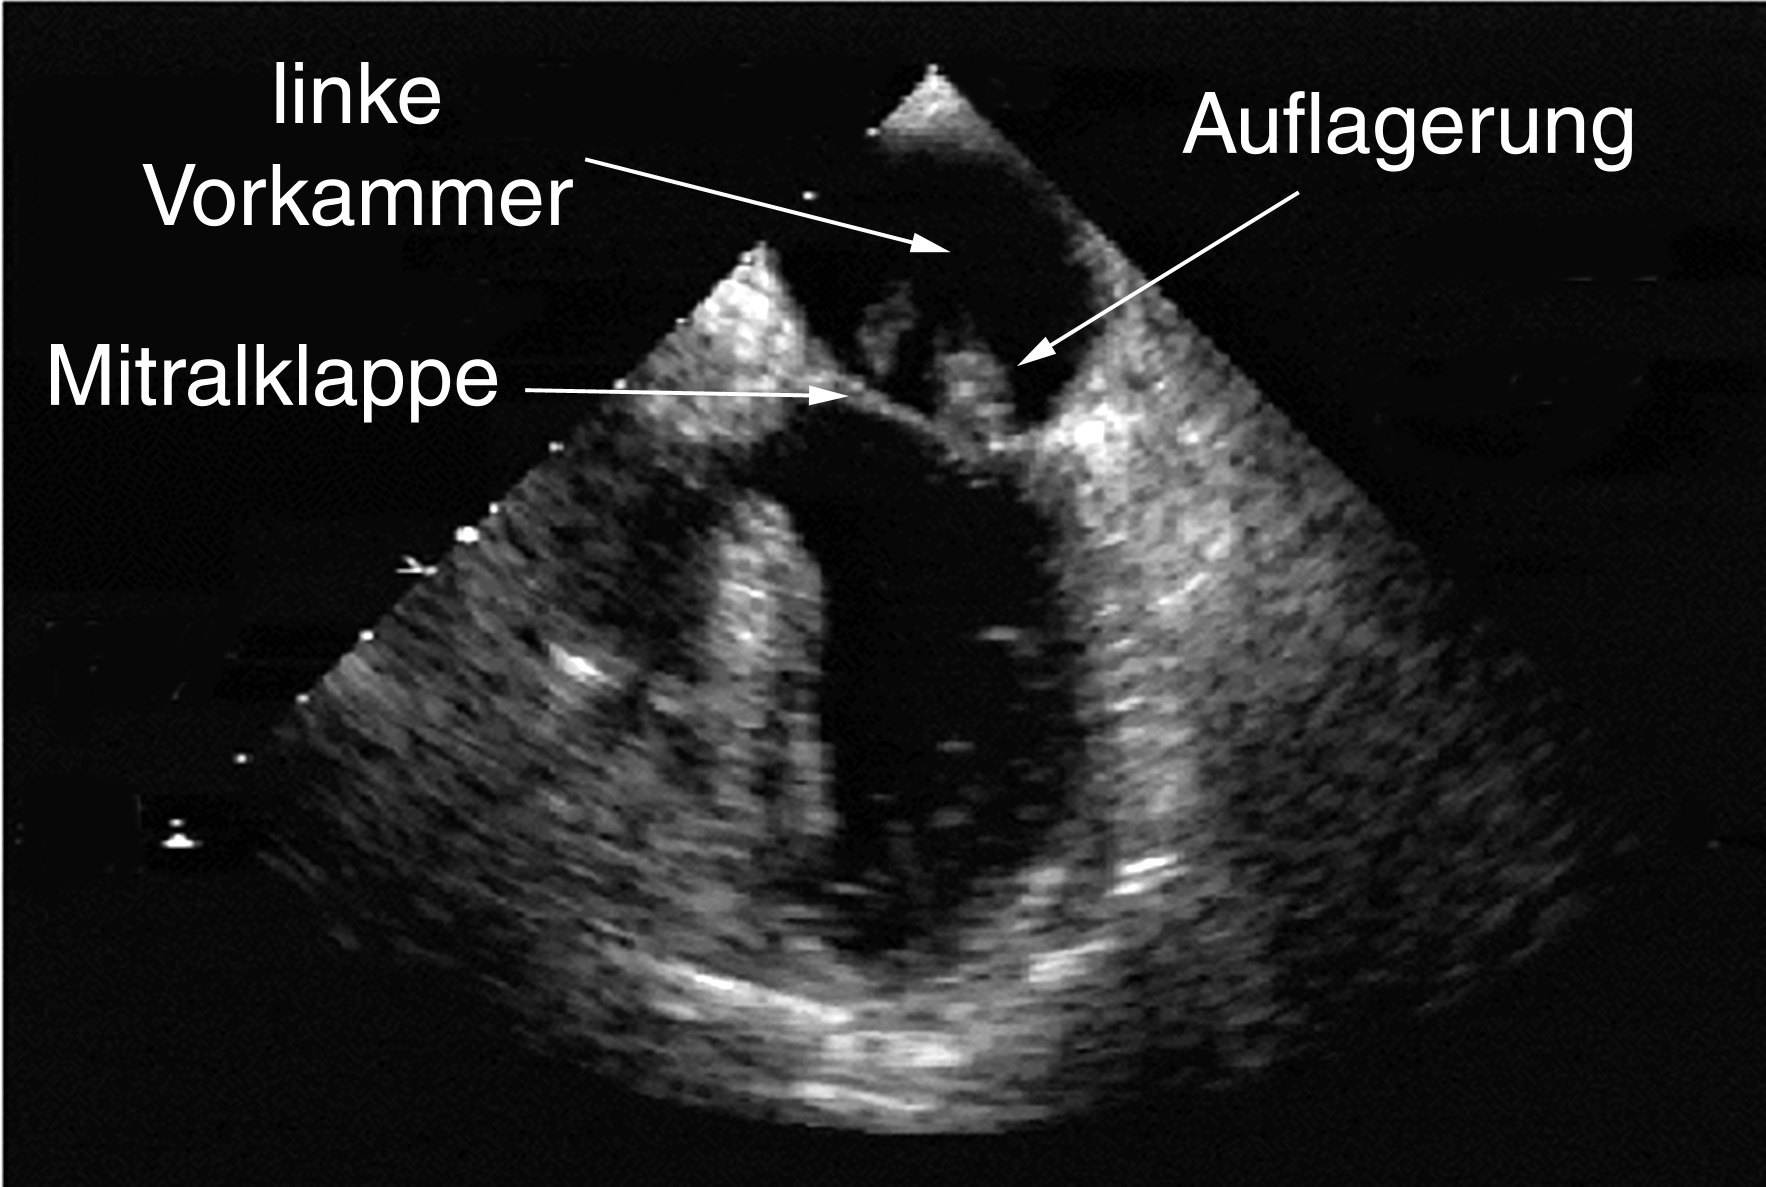

Man kann bei der TEE-Untersuchungen entzündliche Auflagerungen auf den Herzklappen (Abb. links), Löcher in Trennwänden innerhalb des Herzens bei angeborenen Herzfehlern (2. Abb. von links), Gerinnsel in den Herzvor- oder -hauptkammern (2. Abb. von rechts) oder Vergrößerung der verschiedenen Herzhöhlen (Abb. rechts) finden.